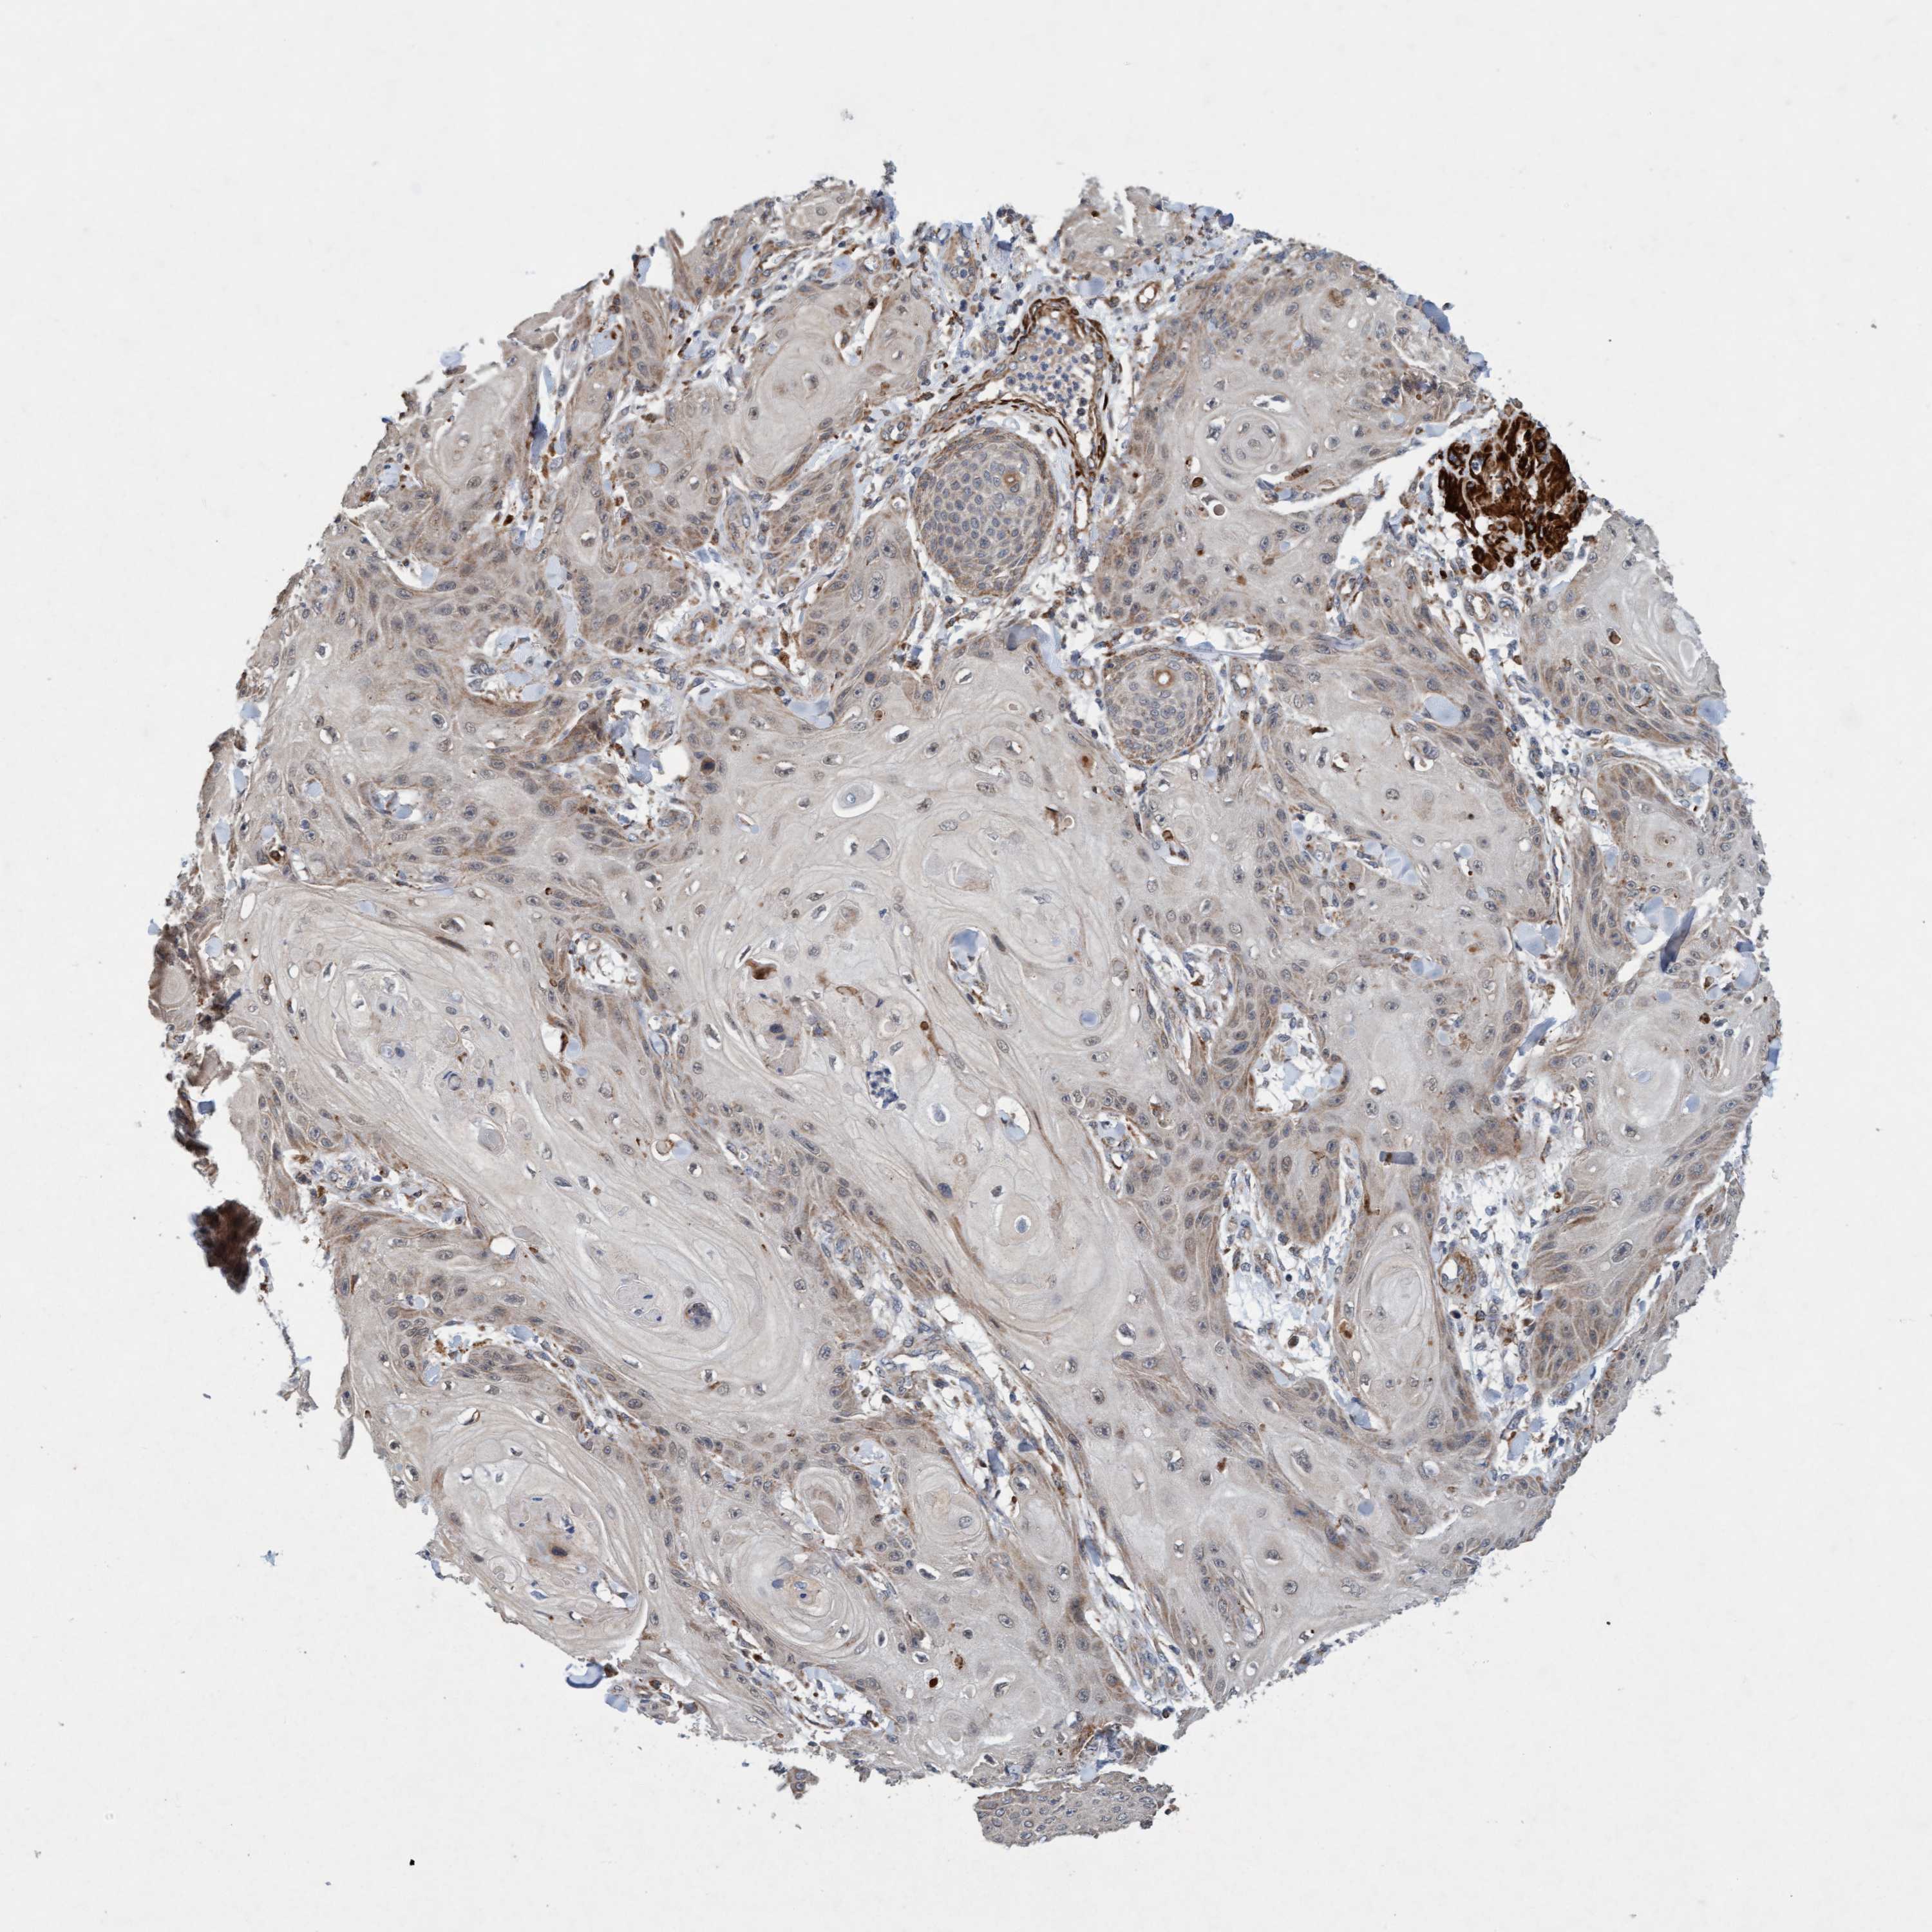

Basal cell and squamous cell cancer

SKIN CANCER - Protein expressioni

A mouse-over function shows sample information and annotation data. Click on an image to view it in a full screen mode. Samples can be filtered based on level of antibody staining by selecting one or several of the following categories: high, medium, low and not detected. The assay and annotation is described here.

Antibody stainingi

Antibody staining in the annotated cell types in the current human tissue is reported as not detected, low, medium, or high, based on conventional immunohistochemistry profiling in selected tissues. This score is based on the combination of the staining intensity and fraction of stained cells.

Each image is clickable and will lead to virtual microscopy that enables deeper exploration of all samples and also displays staining intensity scores, fraction scores and subcellular localization as well as patient and tissue information for each sample.

Antibody HPA023187

Antibody CAB034226

Staining

High

Medium

Low

Not detected

Intensity

Strong

Moderate

Weak

Negative

Quantity

>75%

75%-25%

<25%

None

Location

Nuclear

Cytoplasmic/membranous

Cytoplasmic/membranous,nuclear

Squamous cell carcinoma, NOS

Squamous cell carcinoma, metastatic, NOS